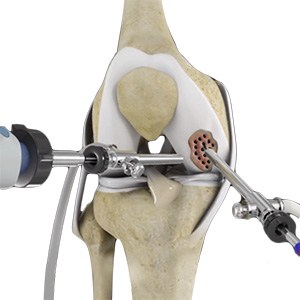

Arthroscopic Debridement

Osteoarthritis is a most common form of arthritis which affects the articular cartilage (tissue covering the ends of the bones) of the knee and also other joints such as shoulder, hip, ankle, and foot. The articular cartilage cushions the joint so that there is smooth and pain-free movement between the bones in the joint.